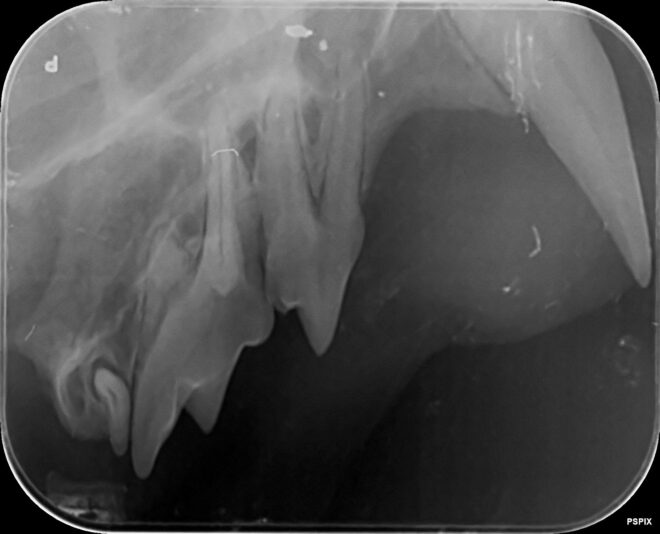

case gegeneraliseerde ontsteking peridontale ruimte

We hebben deze dentale RXen genomen van een jonge oosterse korthaar met chronische gingivitis sinds de geboorte. Op deze Rxen zie ik een verbreed paradontium en een te witte ‘lijn’ bij de aflijning van het alveolair bot. Is er een aandoening die beschreven is bij onze katten en past bij dit beeld? Hoe gaan we verder te werk? Meloxicam lijkt…